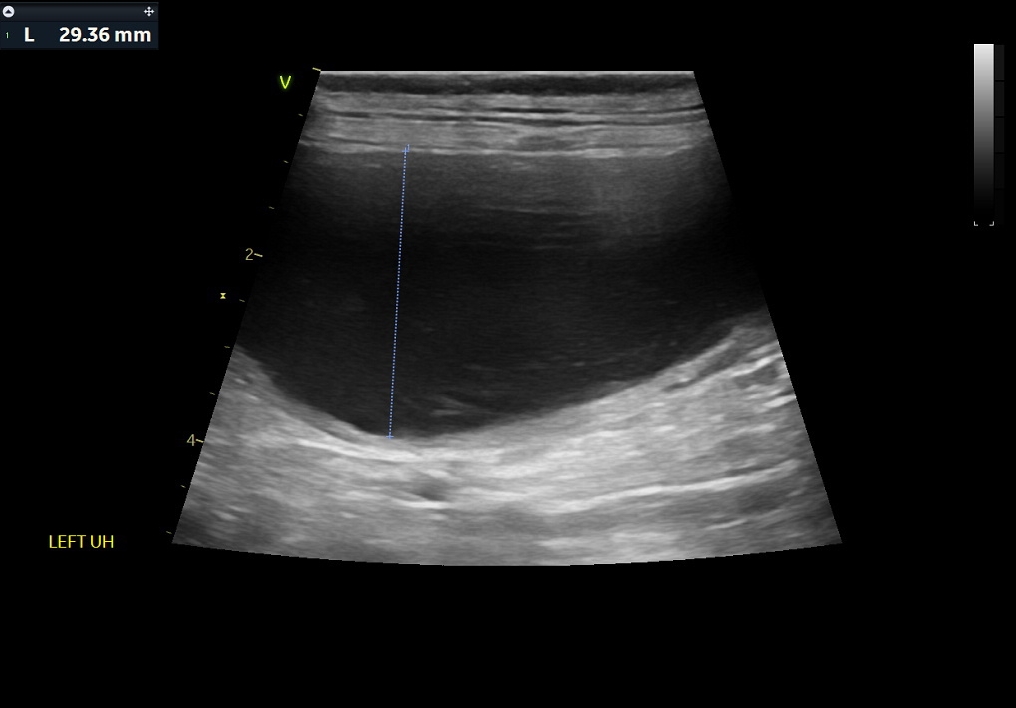

복부초음파 결과 / 출처: 24시온숲동물의료센터

복부초음파·방사선검사 결과

- 내원 당시 시행한 복부 초음파 및 방사선 검사에서 정상적으로는 4mm 정도 두께인 자궁이 약 4cm까지 심하게 확장되어 있는 모습이 확인되었습니다. 내부에는 고름으로 추정되는 내용물이 가득 차 있었으며, 이는 전형적인 자궁축농증의 소견에 해당합니다.